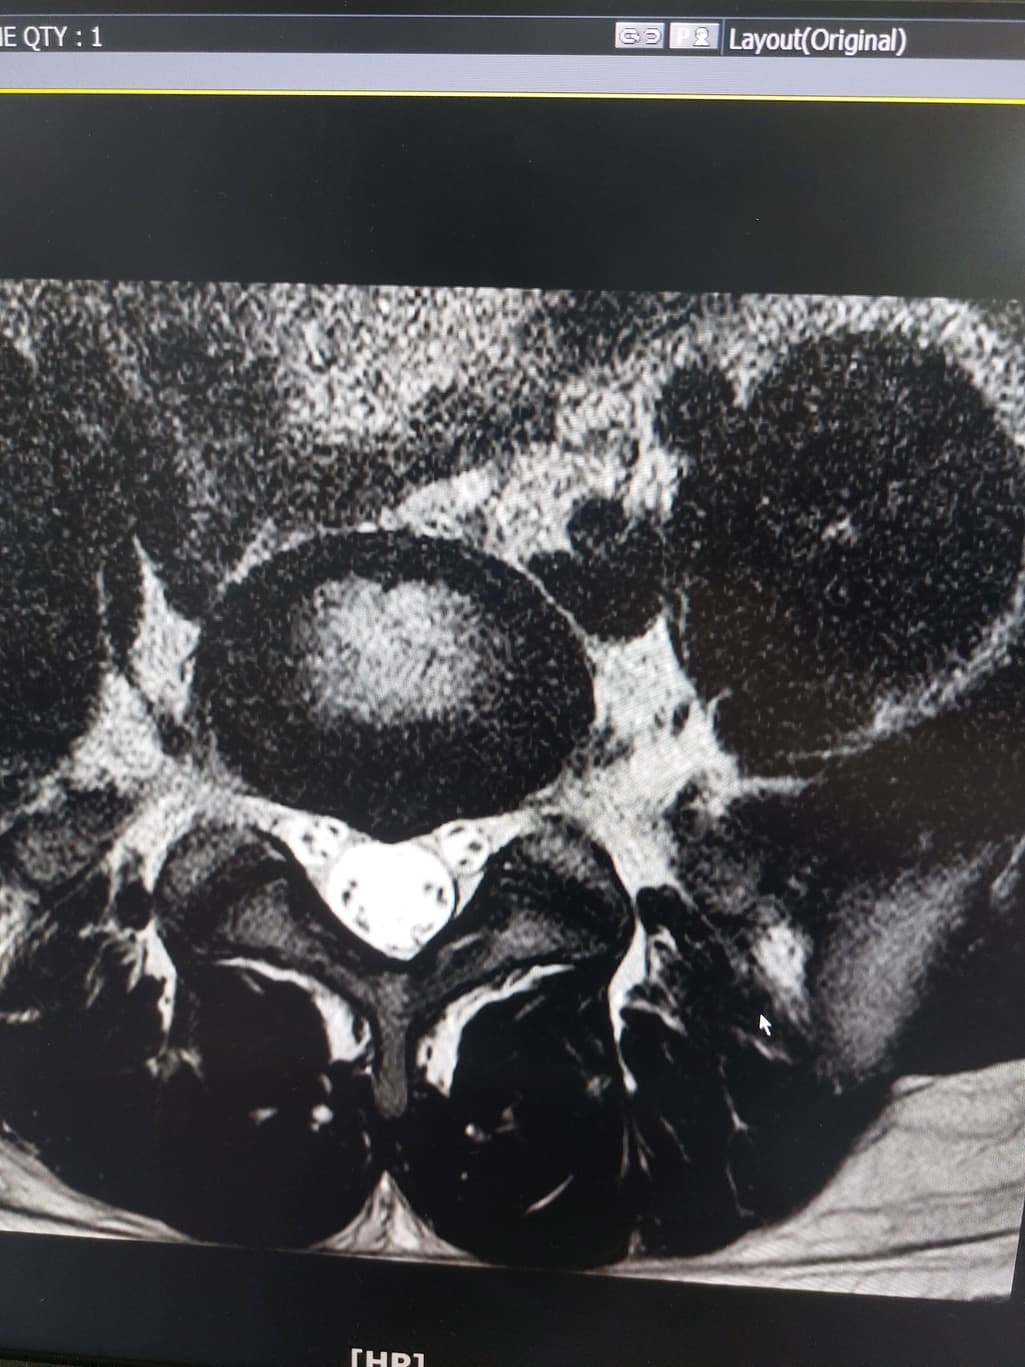

허리디스크 심한편인가요? [Mri 사진 첨부]

멸개월전부터 요추가 뻣뻣하고 시큰거리다가 최근에 좀 나아지긴 해도 만성적이라서 오늘 mri 찍고 허리디스크 진단받았습니다

(요추 맨 밑 천추 위 디스크)

신경이 심하게 눌리고 있지는 않은 것으로 보입니다. 충분히 휴식하여 주시고, 허리에 무리가 많이가는 자세는 당분간은 피해주시는 것이 좋습니다.